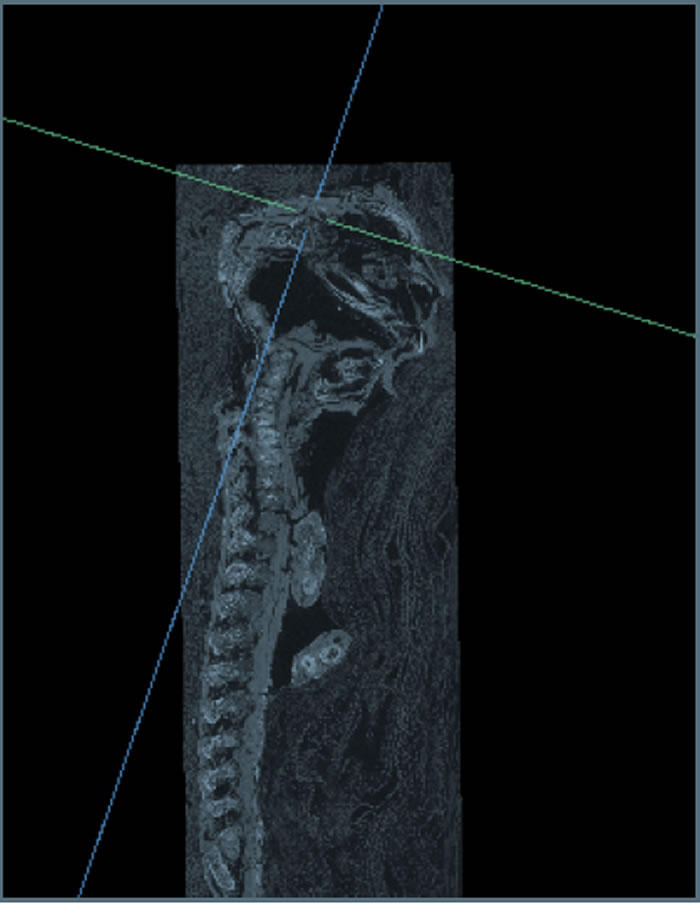

2016年,以安德鲁·纳尔逊为首的西安大略大学团队开始进行研究。借助X射线显微摄影术才弄清楚,这个展品实际上是一个小男孩的木乃伊,他在自己母亲怀孕23-28周时死亡。

在他身上发现了多种疾病,尤其是严重的颅骨变形,同时,骨骼和手指发育良好。专家们认为,就是因为这个死胎的奇怪形态才使其家人将其木乃伊化。顺便要说的是,还有一尊这样的、记载于1826年的木乃伊被科学揭开谜底。